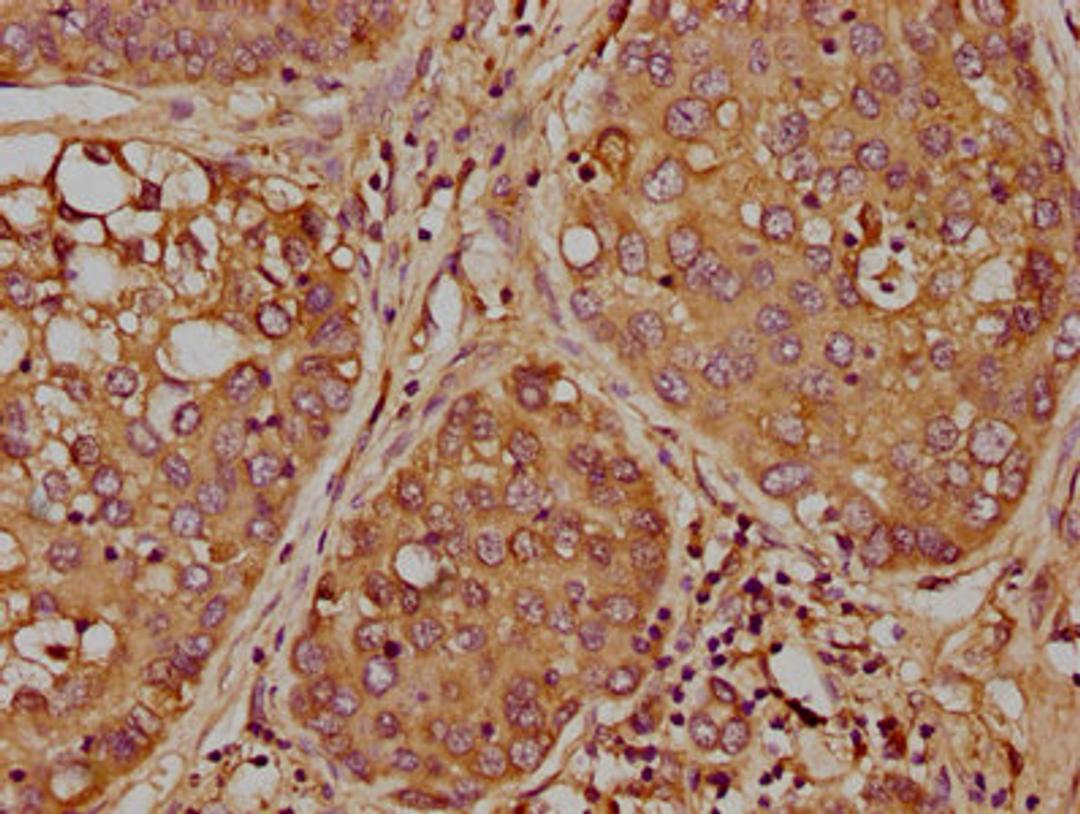

IHC image of CSB-PA857448LA01HU diluted at 1:300 and staining in paraffin-embedded human liver cancer performed on a Leica BondTM system. After dewaxing and hydration, antigen retrieval was mediated by high pressure in a citrate buffer (pH 6.0). Section was blocked with 10% normal goat serum 30min at RT. Then primary antibody (1% BSA) was incubated at 4°C overnight. The primary is detected by a biotinylated secondary antibody and visualized using an HRP conjugated SP system.